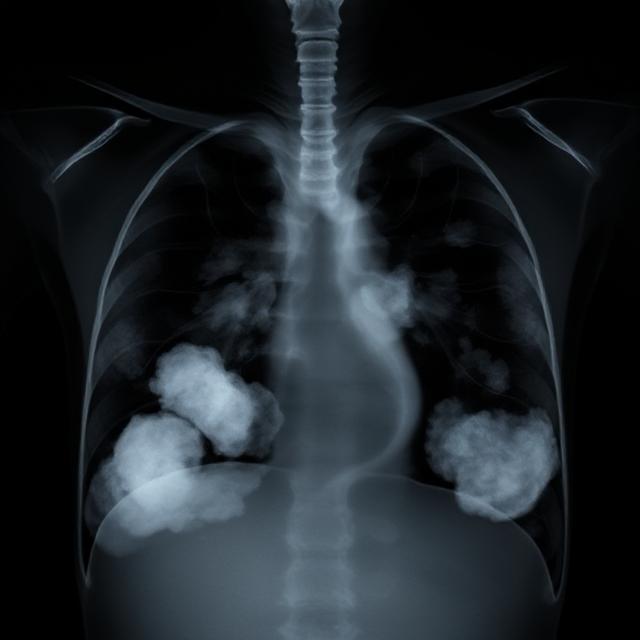

تشخیص به موقع، نقش حیاتی در درمان دارد. پزشک معمولاً از روش‌های زیر استفاده می‌کند:

2. تصویربرداری: رادیوگرافی قفسه سینه یا سی‌تی اسکن برای مشاهده مایع

آب آوردن ریه که در اصطلاح پزشکی به آن پلورال افیوژن گفته می‌شود، یک وضعیت جدی است که در آن مایع در فضای بین ریه و دیواره قفسه سینه جمع می‌شود. این مشکل می‌تواند تنفس را دشوار کند و در صورت عدم درمان به مشکلات جدی‌تری منجر شود. در ادامه، به بررسی علت‌ها، علائم، روش‌های درمان و نکات مراقبتی خواهیم پرداخت.